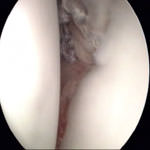

Abb. 5 und 6: Die vordere Gelenklippe (Labrum, links im Bild) ist vollständig von der Pfanne (rechts im Bild) abgelöst. Der Befund kann durch Tasthakenkontrolle bestätigt werden. |